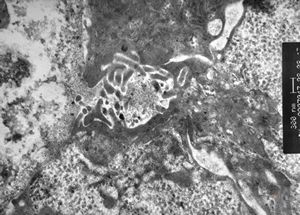

F,7m. | giant cell hepatitis-C-collagen fibers